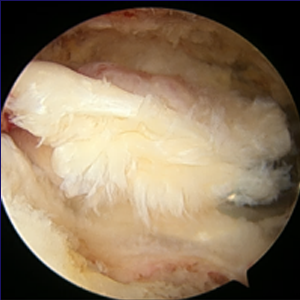

整形外科における手術の役割 肩腱板断裂治療のアルゴリズム 不全断裂 小断裂 中~大断裂 一次修復不能広汎性断裂 保存療法(リハビリ:運動療法/物理療法) 手術療法 関節鏡下腱板修復術 腱移行術、腱移植術、リバース型人工関節 腱板断裂の治療の基本は保存療法ですが、それが反応しない場合には、関節鏡下腱板修復術が適応されます。 修復前 修復後 関節鏡下腱板修復術は「肩に小さな穴を数か所開け、関節鏡で中をのぞきながら縫い合わせる方法」で、私の得意分野です。 不全断裂 小断裂 中~大断裂 一次修復不能広汎性断裂 保存療法(リハビリ:運動療法/物理療法) 手術療法 関節鏡下腱板修復術 腱移行術、腱移植術、リバース型人工関節 縫いきれないほどの大きな断裂には、腱の移植や人工関節が必要になります。 手術を望まない方へは、間葉系幹細胞を用いた再生医療の提供に取り組んでいます。